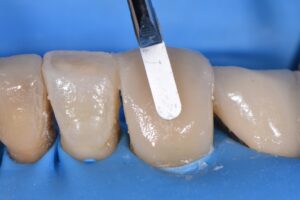

(Afternoon tea pics 1195.7: Garrison Fusion Anterior Matrix | Hu-Friedy Akroflex | Ultradent Dermadam | GC Gaenial A’Chord)

2 S T A G E treatment – This 73 year old male patient suffered from attrition and secondary erosion from a constricted envelope of function. Stage 1: incisal 1/2 treated first under rubber dam but could not gain clamp stability or isolate proximocervically on the root in order to gain access even with brand new Brinker B4s. The proximofacial lesions were restored by first building up the proximal frame utilizing the Garrison Fusion Anterior Matrix System before layering to full volume using the Hu-Friedy Akroflex NiTi brush. Stage 2 cervical abrasion lesions restored with a single shade of A3 G-Aenial A’Chord. Old PFZ restorations recontoured on palatal to allow for greater freedom in the envelope.